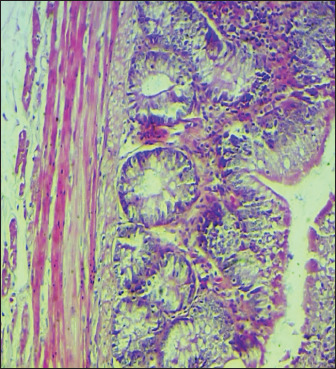

Results: The obtained results showed that broilers that were infected with S. enteritidis and given curcumin and C. myxia did better in terms of body weight, IgG, and IgA levels than the positive untreated group. In particular, C. myxia was better than curcumin in IgA. Even though curcumin or mixed therapy raised glutathione, it also decreased the number of heterophils (heterophilia) and inflammatory cytokines (IL-8 and TNF-α). This happened because the number of white blood cells and lymphocytes was reduced in the groups that got curcumin or C. myxa. The number of goblet cells also was raised. The intestinal villi stayed the same.